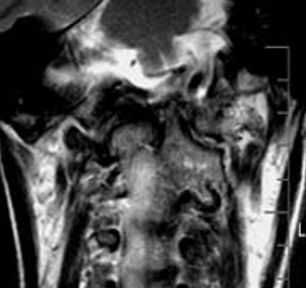

- Исследование можно выполнить в положении сгибания и разгибания, что позволяет оценить стабильность и влияние аномалии на спинной мозг(Слева) На сагиттальном Т2-ВИ, полученном в положении сгибания, видна расположенная несколько кпереди относительно С2 дистопичная зубовидная кость. Сохраняется нормальное расстояние между передней дугой С1 и костью, однако отмечается изменение положения кости относительно С2 (атлантоаксиальная нестабильность) по сравнению с изображениями в нейтральном положении и положении разгибания.

(Справа) Это сагиттальное Т2-ВИ получено в положении разгибания и отражает нормальное расположение зубовидной кости. В положении сгибания эта кость смещается кпереди, что свидетельствует об атлантоаксиальной нестабильности. (Слева) КТ шейного отдела позвоночника, сагиттальный срез: врожденное сращение передней дуги С1 и крупной зубовидной костив. Нормальные взаимоотношения между скатом В и зубовидной костью сохранены. Субаксиальные сегменты шейного отдела позвоночника во всех отношениях нормальны, признаков каких-либо других аномалий сегментации не выявлено.

(Слева) На сагиттальной МРТ (Т2 ВИ) в положении сгибания определяется переднее положение дистопической зубовидной костив относительно С2. Расстояние между передней дугой С1 и зубовидной костью сохранено; определяется нарушение положения зубовидной кош относительно С2 по сравнению с изображениями в нейтральном положении и при разгибании (атланто-аксиальная нестабильность).

(Справа) На сагиттальной MPT (Т2 ВИ) в положении разгибания у этого же пациента положение зубовидной кости обычное. На сагиттальной МРТ (Т2 ВИ) в положении сгибания определялось переднее смещение зубовидной кости, свидетельствующее об атланто-аксиальной нестабильности.2. Рентгенография при зубовидной кости: